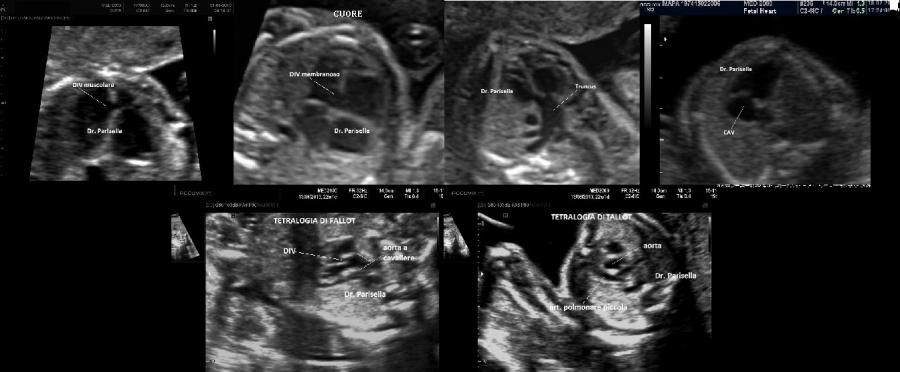

-         Cardiopatie congenite: Tetralogia di Fallot, Ventricolo destro a doppia uscita, anomalie delle vene cave.